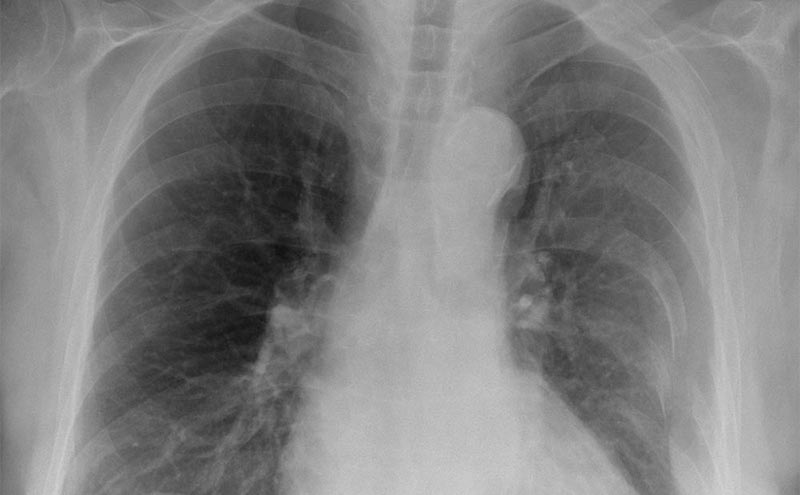

This is a 20 year old male who presents after an MVC. He was the unrestrained driver and was T-boned at approximately 45 mph in an intersection. He complains of pain to his abdomen and chest. He is found to have multiple left sided rib fractures and hemoperitoneum from splenic and liver lacerations. He is hemodynamically stable for EMS but becomes hypotensive and tachycardic in the ED. He should bypass CT and go straight to OR after free fluid found on his EFAST scan. Learners should be able to evaluate a trauma patient as well as perform and correctly interpret EFAST images.